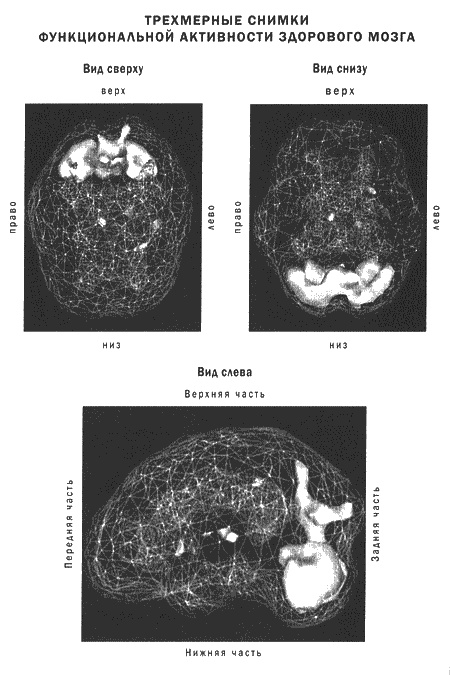

Исследователи сканировали мозг буддистских монахов во время длительной медитации. Чтобы увидеть активность мозга, ученые ввели каждому испытуемому слабый раствор радиоактивных веществ, которые быстро поглощаются нейронами, а их невральная активность отслеживается при этом камерами ОЭКТ. Снимки показали, что при переходе в медитацию в работе мозга происходят отчетливые изменения. В частности, падает активность в областях мозга, которые отвечают за трехмерную ориентацию в пространстве. Это может объяснить ощущение «освобождения» и «парения» во время медитации. Некоторые исследователи предполагают, что элементы религиозных переживаний трансцендентного тоже могут быть заложены в мозге на уровне структур.

В трех следующих главах я расскажу о пяти системах мозга, которые связаны со взаимоотношениями, работой и духовным ростом. Это: кора лобных долей, передняя часть поясной извилины, базальные ганглии, височные доли и лимбическая система. Я расскажу о функционировании и возможных проблемах в работе каждой из этих областей, а также об их роли в восприятии добра, зла, любви и в здоровье души. Разумеется, вся теория будет проиллюстрирована историями и сканограммами ОЭКТ.